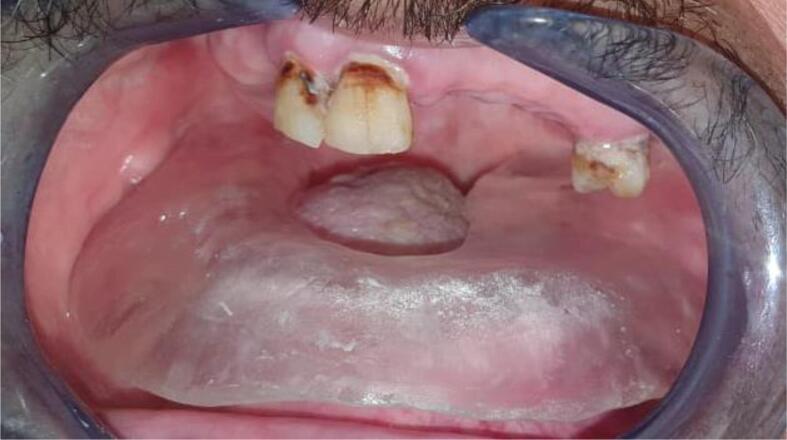

Radiation therapy (RT) is a common modality of treatment in patients with head and neck cancer, and can cause several oral complications. These mainly include radiomucitis, oral pain, hyposalivation, limitation of mouth opening, and osteoradionecrosis.There are different intraoral devices aimed at reducing these complications. It can be used in association with the therapy of RT. They are used to protect healthy tissues surrounding the site to be irradiated, carry the radiation source, move away from certain anatomical structures, position certain devices, and to allow tissue remodeling.The collaboration between the maxillofacial prosthodontist specialist and the radiotherapist is necessary for the design and realization of these devices which differ according to each clinical situation.This work aims to review and illustrate the different radiation devices used in combination with head and neck radiotherapy and introduce a new device design to protect and remove non-radiation-targeted structures.

放射治疗(RT)是头颈癌患者常用的治疗方式,可引发多种口腔并发症。这些并发症主要包括放射性粘膜炎、口腔疼痛、唾液分泌减少、张口受限和放射性骨坏死。有不同的口腔内装置旨在减少这些并发症,可与放射治疗联合使用。它们用于保护待照射部位周围的健康组织、携带放射源、远离某些解剖结构、定位某些装置以及促进组织重塑。颌面修复专家与放射治疗师之间的合作对于设计和制作这些因临床情况而异的装置至关重要。本研究旨在回顾和阐述与头颈放疗联合使用的不同放射装置,并介绍一种用于保护和移开非放射靶结构的新装置设计。